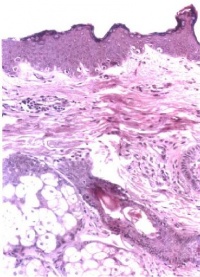

面神经炎在脑神经疾患中较为多见,这与面神经管是一狭长的骨性管道的解剖结构有关,当岩骨发育异常,面神经管可能更为狭窄,这可能是面神经炎发病的内在因素。面神经炎发病的外在原因尚未明了。有人根据其早期病理变化主要为面神经水肿髓鞘及轴空有不同程度的变性,推测可能

面神经水肿透视

因面部受冷风吹袭,面神经的营养微血管痉挛,引起局部组织缺血缺氧所致。也有的认为与病毒感染有关,但一直未分离出病毒。近年来也有认为可能是一种免疫反应。膝状神经节综合征(Ramsay-Hunt Syndrome)则系带状疱疹病毒感染,使膝状神经节及面神经发生炎症所致。